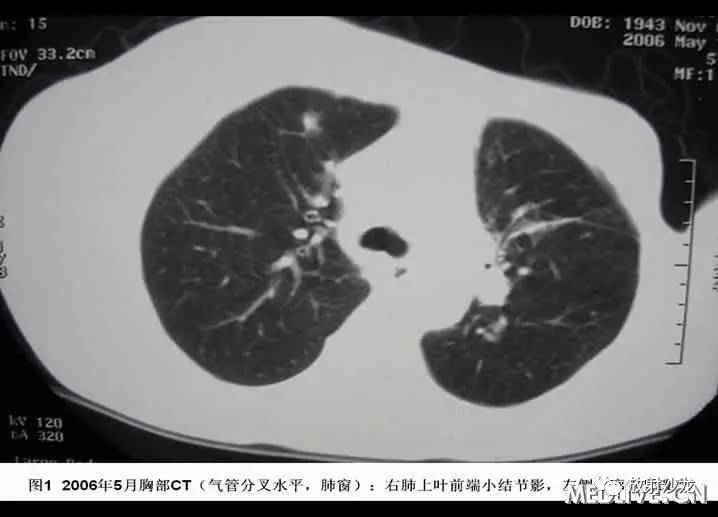

患者于2006年4月初无诱因出现间断咳嗽,少量黄痰,无咯血、胸闷、胸痛。2006年4月中下旬出现发热,最高体温38℃,当地血常规:WBC:6.7G/L,GR:78%,胸片示“右下肺纹理增粗,局部可见斑片索条影,右侧肋膈角钝”;考虑“肺部感染”,予拜复乐(莫西沙星)、罗氏芬(头孢曲松)治疗3天后体温降至正常,但仍有间断咳嗽、咯痰,遂于2006年5月中旬就诊某一上级医院,胸部CT“右下肺及胸膜下可见多发结节、斑片影,局部可见支气管扩张”(见图1-4),行胸腔镜肺活检,病理经多家医院综合会诊后考虑“淋巴组织增生性病变,但是诊断淋巴瘤证据不够”,未予特殊治疗。

2007年3月中旬因再次高热,最高体温达38.5℃,咳嗽、咯痰、呼吸困难症状加重,复查胸部CT,提示肺内病变较前明显加重(见图5-8),行CT引导下左肺阴影穿刺活检,但未能明确诊断而收住。起病以来,食欲差,乏力明显,出汗多,夜间能平卧。无皮疹、关节痛,体重降落近20Kg。